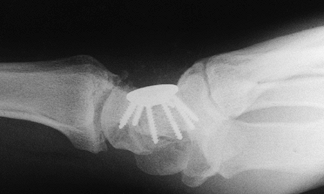

Fix the remaining four carpal bones. Confirm proper position with a radiograph. K-wires (Fig. 72.11),

Herbert and other types of screws, and, recently, new plate–screw

systems have been used to provide fixation and allow early mobilization

(Fig. 72.9, Fig. 72.10). After

![]() |

|

Figure 72.9. Capitohamate triquetrolunate intracarpal arthrodesis with spider plate fixation.

Figure 72.10. Capitohamate triquetrolunate intracarpal arthrodesis with spider plate fixation, lateral view.